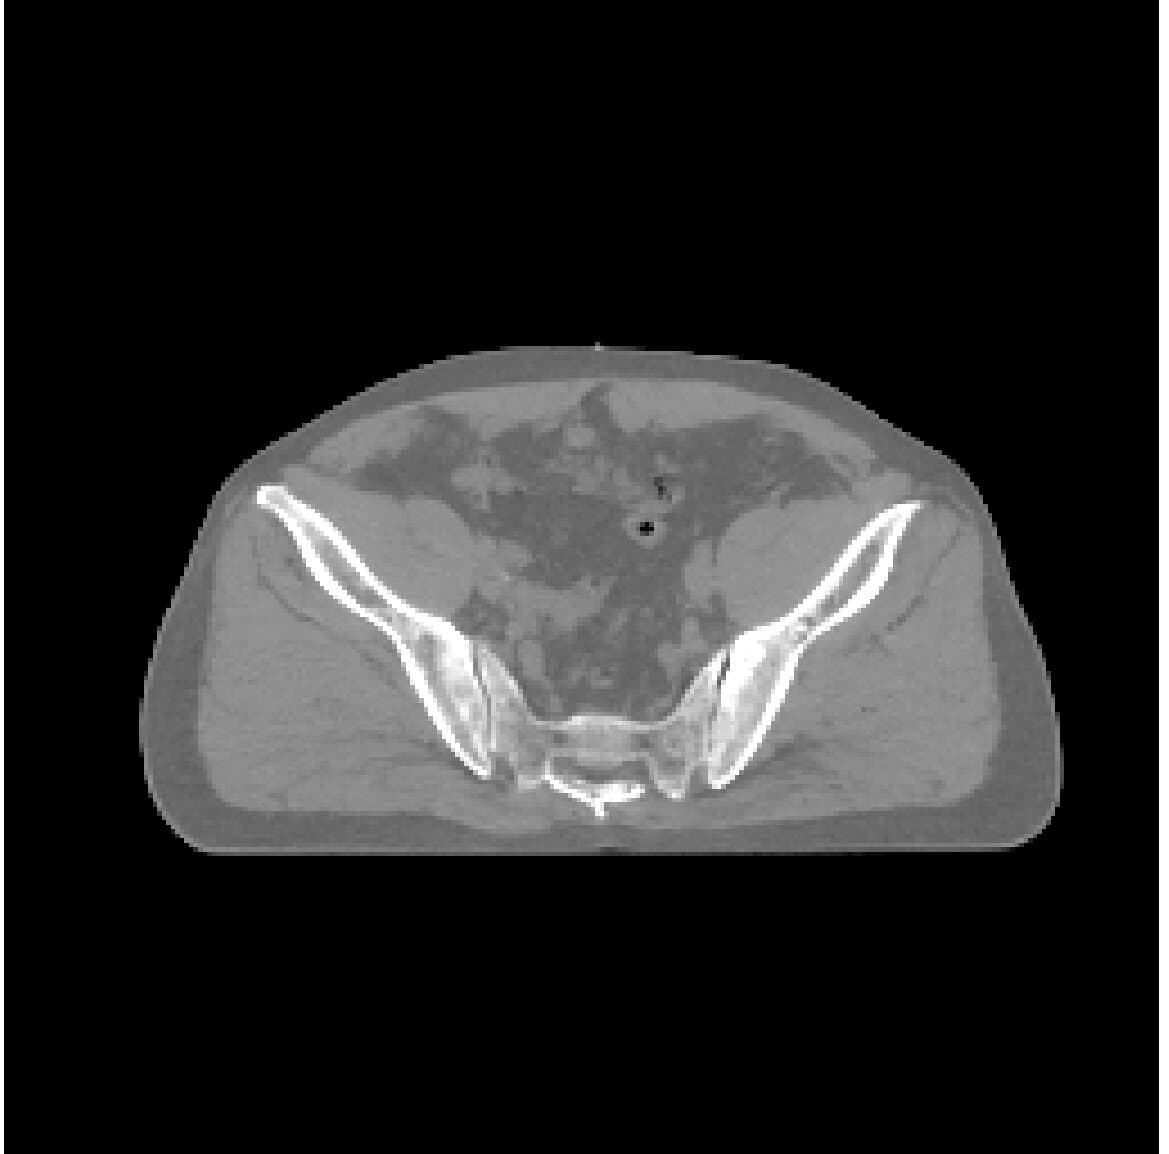

CycleDPM is a dual-stage diffusion model framework for anatomy-preserving CBCT-to-CT image synthesis, designed for adaptive radiation therapy. CBCT images suffer from noise and scatter artifacts that degrade their clinical utility, and CycleDPM corrects these artifacts to synthesize high-quality CT images directly from CBCT scans.

The method achieves state-of-the-art quantitative results with MAE: 67 -> 46.9 [HU] and SSIM: 0.845 -> 0.902, outperforming GAN-based baselines. The work was presented at ICNGC 2025 and is currently being prepared for broader publication.

Compare the original CBCT slice with the synthesized CT output using a draggable divider and a direct slider control.

Use the handle or the range control to compare CBCT and synthesized CT.